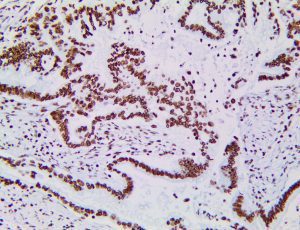

It is the ICU physician who is most likely to witness one of the deadliest manifestations of the abnormal immunological response, the cytokine storm syndrome (CSS). This response is also referred to by some as the cytokine release syndrome (CRS). CSS is characterized by continuous activation and expansion of macrophage and lymphocyte populations, which secrete large amounts of cytokines, causing the cytokine storm. This massive cytokine release is akin to hemophagocytic lymphohistiocytosis (HLH) disease, a syndrome characterized by initial unchecked and persistent activation of cytotoxic T lymphocytes and NK cells.

Clinical and laboratory manifestations of HLH include fever, enlarged liver and/or spleen, neurologic dysfunction, coagulopathy, liver dysfunction, cytopenias (i.e., low levels of erythrocytes, leukocytes, and/or platelets), hypertriglyceridemia, hyperferritinemia, hemophagocytosis, and eventually diminished NK cell activity as the immune system becomes progressively paralyzed. HLH can be familial (primary HLH) or secondary to another disease process (sHLH), such as rheumatic disease, in which it is referred to as macrophage activation syndrome (MAS, characterized by elevated ferritin).